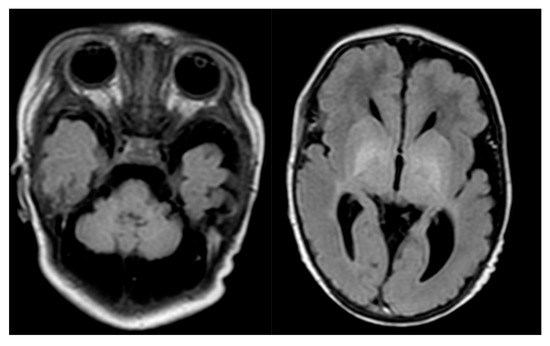

Molybdenum cofactor (Moco) deficiency (MoCD) is characterized by neonatal-onset myoclonic epileptic encephalopathy and dystonia with cerebral MRI changes similar to hypoxic–ischemic lesions. The molecular cause of the disease is the loss of sulfite oxidase (SOX) activity, one of four Moco-dependent enzymes in men. [...] Read more.

Molybdenum cofactor (Moco) deficiency (MoCD) is characterized by neonatal-onset myoclonic epileptic encephalopathy and dystonia with cerebral MRI changes similar to hypoxic–ischemic lesions. The molecular cause of the disease is the loss of sulfite oxidase (SOX) activity, one of four Moco-dependent enzymes in men. Accumulating toxic sulfite causes a secondary increase of metabolites such as S-sulfocysteine and thiosulfate as well as a decrease in cysteine and its oxidized form, cystine. Moco is synthesized by a three-step biosynthetic pathway that involves the gene products of MOCS1, MOCS2, MOCS3, and GPHN. Depending on which synthetic step is impaired, MoCD is classified as type A, B, or C. This distinction is relevant for patient management because the metabolic block in MoCD type A can be circumvented by administering cyclic pyranopterin monophosphate (cPMP). Substitution therapy with cPMP is highly effective in reducing sulfite toxicity and restoring biochemical homeostasis, while the clinical outcome critically depends on the degree of brain injury prior to the start of treatment. In the absence of a specific treatment for MoCD type B/C and SOX deficiency, we summarize recent progress in our understanding of the underlying metabolic changes in cysteine homeostasis and propose novel therapeutic interventions to circumvent those pathological changes. Full article